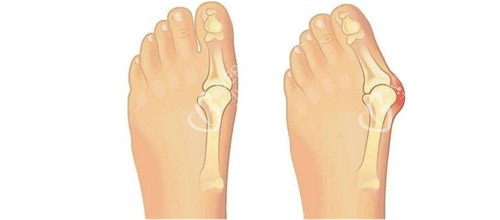

在追求美丽与健康的道路上,大脚骨问题成为了许多人的困扰。它不仅影响足部美观,还可能引发疼痛与功能障碍。北京广济医院凭借其在大脚骨治疗领域的卓然表现,成为了众多患者的信赖之选。下面,让我们深入了解一下这家医院。

北京广济医院是一家集医疗、教学、科研于一体的现代化综合性医院,位于北京市丰台区。它是经过卫生部门批准的正规医疗机构,也是北京市社会医疗保险机构定点单位。医院在足踝专科领域扎根近二十年,院内专设 “拇外翻小创口矫正中心” 和 “足踝功能重建科”,年手术量超 1500 例,专科属性强。此外,医院配备了德国卡瓦三维 CT、美国 Stryker 关节镜等智能化设备,为比较准治疗提供了有力维持。

医院重视患者的个体差异,针对不同病情和体质的患者,制定个性化的治疗方案。对于轻度外翻患者,可能建议采用支具调整结合改善训练;而中重度患者则需通过手术矫正骨骼和软组织平衡。这种个性化的治疗方案满足了患者的需求,确保了手术结果的满意度和自然度。